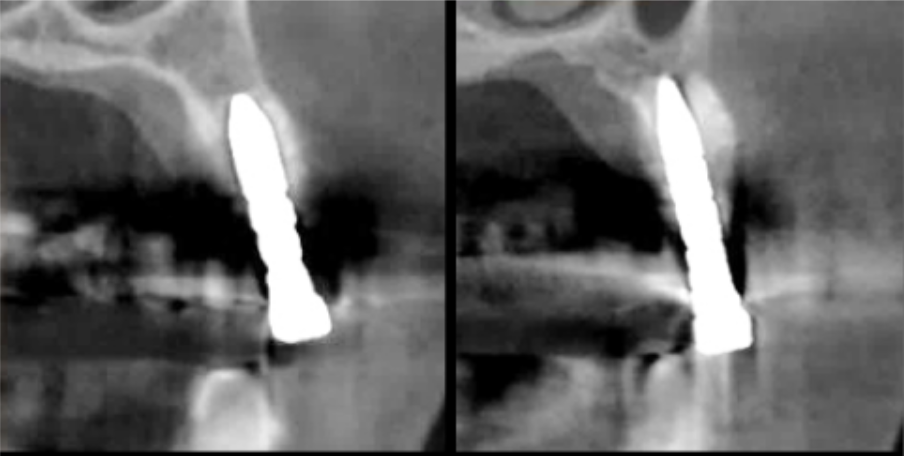

インプラント埋入前のCTによる確認